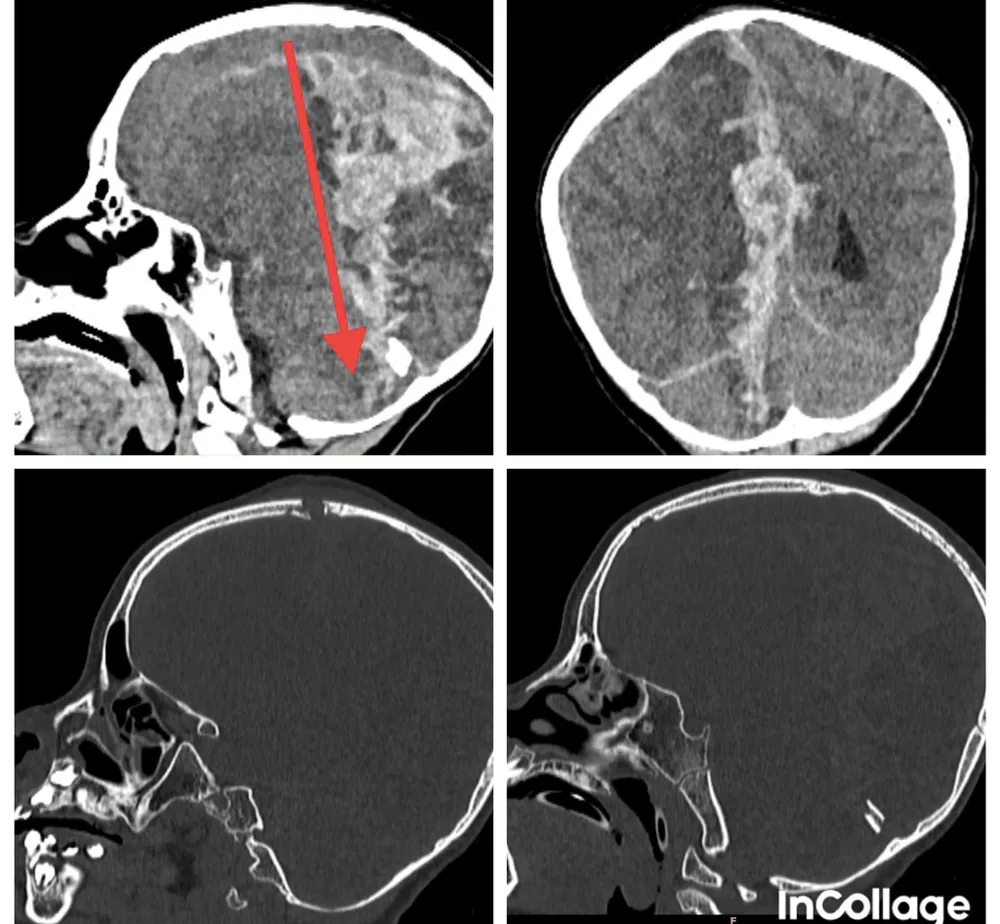

CT-scan ghi nhận tổn thương xuyên thấu qua não từ phía trước đỉnh đầu xuyên ra đến phần tiểu não phía sau, gây xuất huyết dưới màng cứng và trong não lượng nhiều, chèn ép và phù não.

Sau khi tiếp nhận bệnh nhi, đội ngũ y bác sĩ BV Nhi đồng 2 lập tức thực hiện phẫu thuật khẩn cấp để lấy máu tụ và mở sọ giải áp.